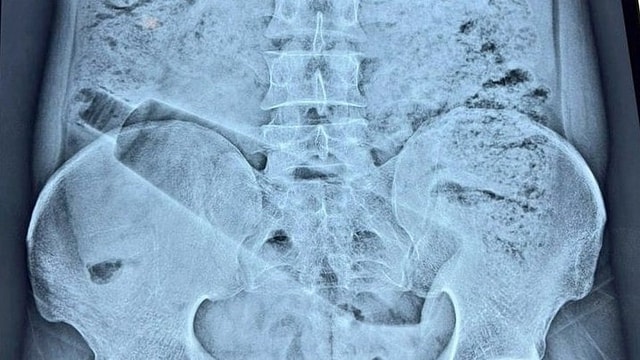

Người đàn ông 38 tuổi, cư dân của khu Saket Colony, được cho là đã bị đau bụng dữ dội trong gần 36 giờ trước khi được đưa đến một bệnh viện tư nhân. Thăm khám ban đầu và chụp X-quang cho thấy một chai nhựa dung tích một lít bị mắc kẹt bên trong cơ thể ông.

Theo bác sĩ phẫu thuật cấp cao Sunil Sharma, trường hợp này rất nhạy cảm do nguy cơ tổn thương ruột và trực tràng trong quá trình phẫu thuật. Một nhóm bác sĩ đã tiến hành ca phẫu thuật được lên kế hoạch cẩn thận, kéo dài khoảng 1 giờ 10 phút, để lấy dị vật ra một cách an toàn.